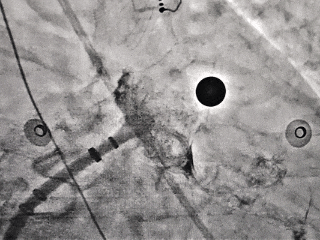

DSA造影+测量

DSA下心耳开口29.7mm,深度23mm;

综合测量结果,选择MemoLefort LAFDQ-32封堵器进行对共干区域进行封堵。

展开封堵器后牵拉试验并造影

牵拉试验

封堵器顺应心耳形态,稳定锚定

多切面造影确认,封堵完全,无残余分流

展开后DSA下充分评估

压缩比10.6%,在8%-30%之间,符合推荐压缩比

封堵器释放后造影,无残余分流